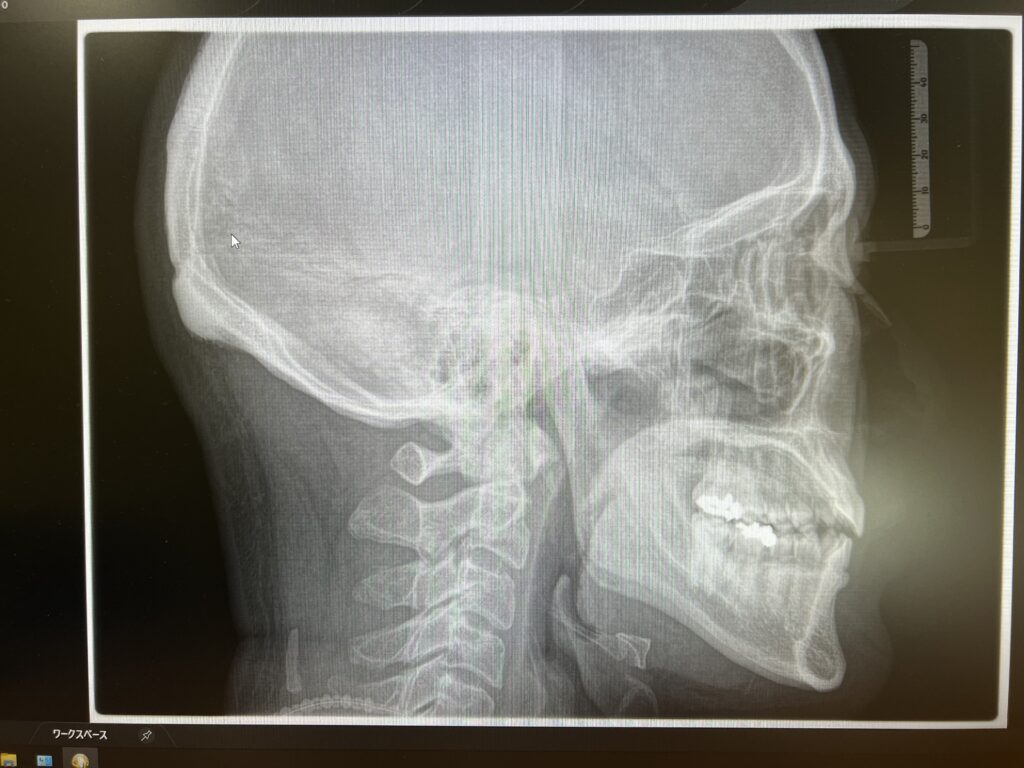

セファロ:主に矯正治療(←押して頂くと矯正ページへ)の際に使う規格化されたレントゲン撮影で、一定の距離と顔の傾きなどを出来るだけ合わせて撮影し、歯の傾きや骨格的な問題などの診断、矯正前後の比較をするためのレントゲン

顎関節の状態や、矯正の際に骨格を診断するセファロ撮影なども可能です。

他にCT撮影ではないですが、今回セファロと呼ばれる規格写真撮影もオプションで取り付けて撮影が可能となっているので

このようなレントゲン撮影も可能で、骨格的な問題を考えて矯正治療などを行います。